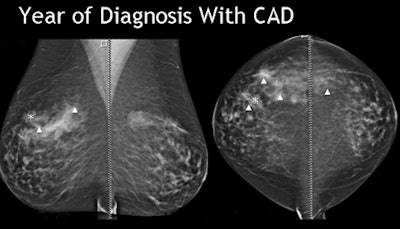

| Breast cancer detected by CAD in prior year's mammogram was ignored by the reader. All images courtesy of Dr. Stamatia Destounis. |

The study evaluated the effectiveness of digital mammography CAD in marking breast cancers both at diagnosis and in prior years' scans. The retrospective review examined all interval missed cancers from 2004-2008, Destounis said.

At diagnosis CAD marked 78% (47) of the cancers, Destounis said. CAD marked 70% of the masses, 80% of masses with calcium, and missed the case of architectural distortion.

"CAD marked the area of cancer 47% of time (n = 24) on the prior most recent mammo, and in fact there was one case where the cancer was marked on two prior years," Destounis said. But in all cases of prior findings, either "we didn't pick it up or we didn't mark it," she said.

Overall, CAD marked the cancer 78% of the time, and cancer in prior year(s) 40% of the time, she said. So the study showed that even when CAD marked the lesion of interest, radiologists continue to disregard the CAD marks frequently, she said. Why is this happening?